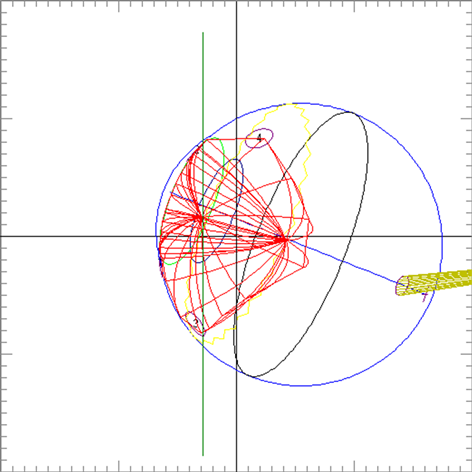

Clinical relevance of the extended distal range in silicone was studied for impact in EYEPLAN treatment planning software, including cases in which tumors were in close proximity to the optic disc/nerve and macula as well as cases in which anterior ciliary body tumors were treated. To demonstrate the necessity of the dosimetry measurement in silicone oil, we present an example of a patient with a ciliary body tumor in the right eye that is relatively amelanotic and involves the iris root but does not involve the angle. The dimension of the tumor is 13 × 8 × 8.7 mm3 (tumor height of 8.7 mm). Figure 5(a) shows the beam’s-eye-view (BEV) of the treatment plan, using gaze direction having polar and azimuth angle of (30˚, 135˚). The patient is looking towards the upper right-hand corner of the box (up and out). The range of the beam is 14.7 mm and SOBP is 16 mm. The aperture contour around the tumor represents the 50% isodose line. The optic nerve and macula are behind the tumor and receiving no proton dose, while some portion of the lens is within the 50% isodose line. This can be clearly seen from Figure 5(b) which shows the treatment plan in the lateral view. Figure 6(a) shows the dose distribution in the fundus view for a normal eye and figure 6(b) shows the dose distribution in the fundus view for a silicone oil filled eye, with adjusted proton range. Figure 7(a) and Figure 7(b) are the respective dose volume histograms (DVHs) for the two scenarios of a normal water-equivalent eye (7a) and a silicone-filled eye with potential proton range impact (7b). In this case as seen from Figure 6(a) and Figure 7(a), optic disc, macula and optic nerve gets 0 dose in the normal eye. If the eye were to be filled with silicone oil, the range of the beam would increase by 2mm. In that case as seen from Figure 6(b) and Figure 7(b), the dose to 50% area of the disc would increase by 50% of the total dose (i.e. 28 GyE in this simulation). A length of 0.4 mm of the optic nerve would receive 50% of the total dose (Figure 7(b)) as compared to the treatment plan if the eye is filled with water (Figure 7(a)). The doses to the structures of the eye in two scenarios are summarized in Table 3.

Figure 5. (a) The illustration of the treatment of uveal melanoma of the right eye in beam’s-eye-view using gaze direction having polar and azimuth angle of (30˚, 135˚). The patient is looking towards the upper right-hand corner of the box (up and out). The aperture contour around the tumor represents the 50% isodose line. The optic nerve and macula are posterior to the tumor, while a portion of the lens is in the field. (b) Shows the treatment plan in the transverse plane. The optic nerve and macula are estimated at 7 mm and 10 mm from the tumor.